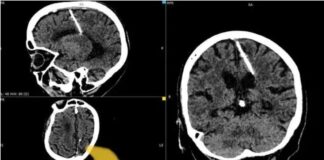

Etichetă: ac în creier